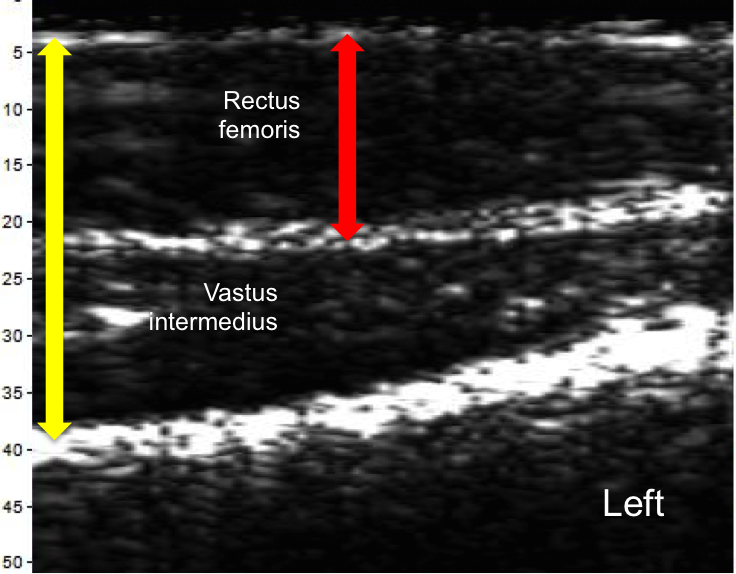

Muscle Imbalance

The scans below taken of the left and right quadricep from the midpoint to near the patella were recorded on the same day. The scans show clear differences. The yellow and red arrows represent the same thickness in each image, showing significant imbalance. The ratio of the Rectus Femoris thickness to the Vastus intermedius is 1.3 for the left leg and 0.8 for the right leg.